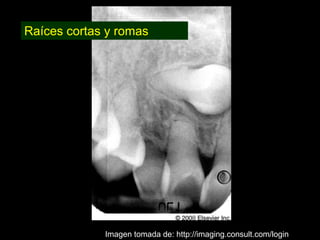

Dentinogénesis imperfecta es una condición genética que causa un disturbio en la formación de la dentina. Existen tres tipos principales. El tipo I se asocia con osteogénesis imperfecta. El tipo II solo afecta la dentina y causa dientes amarillos o grises con atrición. El tipo III es raro y se encuentra en un área aislada de Maryland, con exposiciones pulpares frecuentes. Todos los tipos muestran características radiográficas como obliteración de cámaras y conductos,